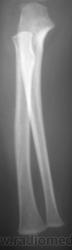

Травма.   Ребенок направлен на рентгенографию костей предплечья и локтевого сустава.

Поднадкостничный перелом в/3 лучевой кости.

Я думаю,что в с/3 нет перелома,скорее всего полосы просветления-тени сосудистых каналов,может я и не права.